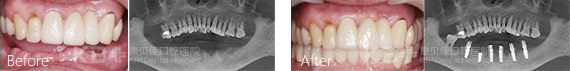

即刻种植牙适应症广,特别是半口或者全口牙缺失,康贝佳口腔给您推荐ALL-ON 4种植技术。ALL-ON 4只需四颗种植体即可恢复半口牙,大大节省了费用。并且ALL-ON 4种植牙无骨量限制,再糟糕的口腔环境也能成功种上一口好牙。